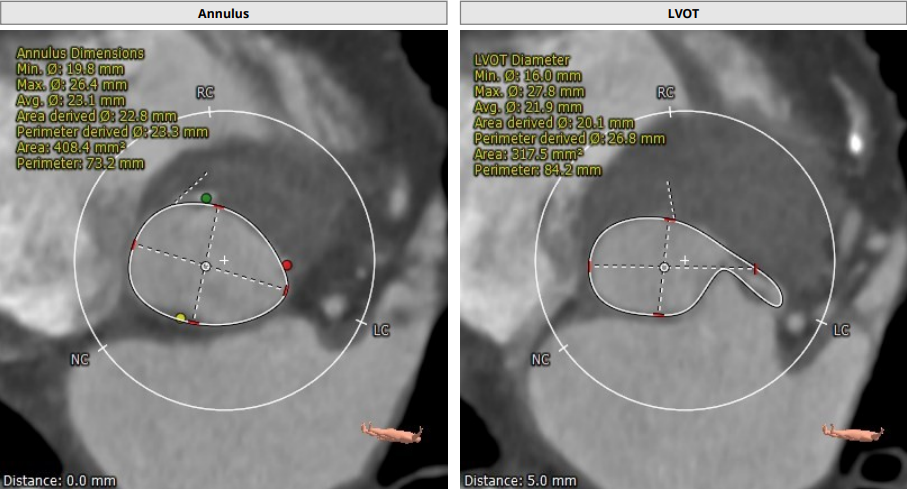

主动脉根部:

Annulus:23.3 mm,LVOT:21.9 mm,STJ:30.8 mm,Asc.AO:43.5 mm

LCA:13.2 mm,RCC:14.0 mm

瓣环及左室流出道呈开放式结构

TYPE1 型二叶瓣,重度钙化,钙化呈单边分布,主要集中在无冠窦侧,左右可见非钙化脊,左冠高度约 13.2 mm,右冠高度约 14 mm,法式窦结构大,STJ 高度约 19.4 mm、直径约 30.8 mm,升主动脉可见增宽,最宽处约 47.1 mm,心脏角度约 46°,左室大小可,右窦居中体位:RAO4°、CAU21°,左冠切线位:LAO2°、CAU16°。